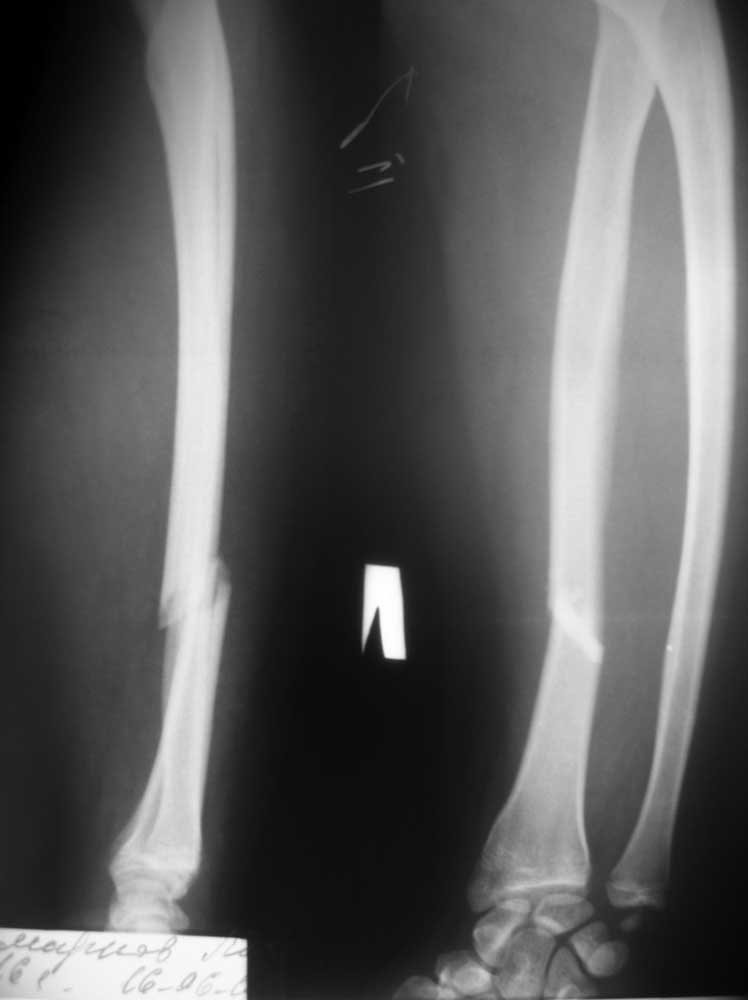

Классический перелом Голлеаци с повреждением дистального лучелоктевого

сочленения. Невозможно вправить вывих без восстановления длины луча.

Абсолютное показание к открытой репозиции луча со стабильной фиксацией

(пластинка).